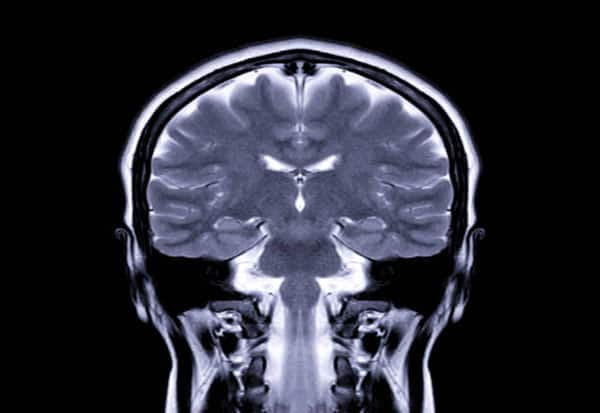

New Delhi: A faster-than-normal development of brain could be a possible reason for humans to develop intellectual disabilities or autism, according to a study.

Brain cells or neurons, especially those in the cognition region -- the cerebral cortex -- take years to fully mature, a process called 'neoteny' and known to be critical for developing advanced cognitive (thinking) processes distinct to humans.